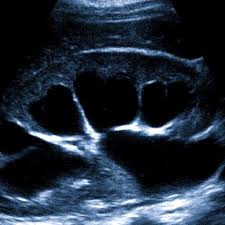

Диагностика начинается с беседы с врачом. Уролог или нефролог уточняет симптомы, образ жизни, перенесённые инфекции. Затем назначают лабораторные и инструментальные обследования. Самое простое — ультразвуковое исследование (УЗИ). Оно показывает увеличение почки и расширение её лоханки. В сложных случаях делают компьютерную томографию (КТ) или урографию с контрастом. Это помогает определить степень поражения и причину задержки мочи.

- УЗИ почек и мочеточников.